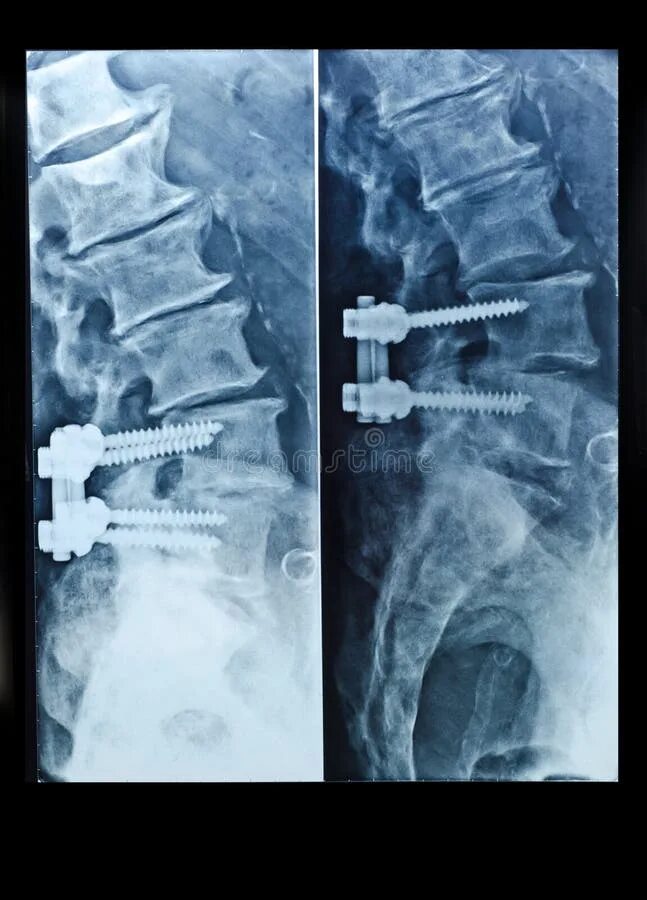

Установка кейджа в позвоночнике